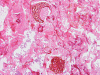

Pathology of the Case: Multiple tissue samples were from several locations of the sinuses were rerceived. The specimen was in the form of small aggregates of irregularly shaped, tan brown, necrotic debri with clotted blood and purulent material. Admixed with the soft tissue were small fragments of bone. Frozen section of “left nasal contents” reveals fungal organisms with hyphae and nonviable collagenous tissue, suspicious for invasive fungal infection. On permanent sections, about 99% of the tissue is composed of necrotic debri. There is an abundance of fungal organisms.  While some of the organisms are scattered, there are areas suggestive of an angioinvasive pattern. These organisms may well be recognized by hematoxylin and eosin stain but also well demonstrated by PAS and GMS stain. The organisms contain pauciseptate, “ribbon-like,” irregular hyphae with acute and right-angle branching. Associated with the hyphae are globus-shaped, pigmented sporangia  and columella (Panel C, D, and E). The hyphae are wide and here show acute angle branching. Occasional septum can be seen (Panel  D and E). The sporangium on the left shows angulated sporangiospores (Panel C and E). These features are characteristic of the class Zygomyycetes, order Mucorales. This order includes the Rhizopus and Mucor species. Fungal culture identified a Rhizopus specie as well as Aspergillus. The pathologic features are most compatible with a sino-nasal mixed fungal infection in an immunocompromised host.

All Zygomycota share similar morphologic features with broad, thin-walled, pauciseptate hyphae. Typically the different genera can be separated by the appearance of their sporangia and sporangiophores grown in culture media. In this case, the globus shape and brown pigmentation of the sporangia along with the angulated shape and striations of the sporangiospores are consistent with the diagnosis of Rhizopus species. In the rare instance that these features are identified on tissue section, a presumptive diagnosis can be made. This diagnosis should be followed up by fungal culture confirmation. Diagnosis and management of fungal infection in immunocompromised patients often requires a multidisciplinary approach. Careful histologic evaluation may provide early identification of mucormycosis and save valuable time in directing focused therapy.